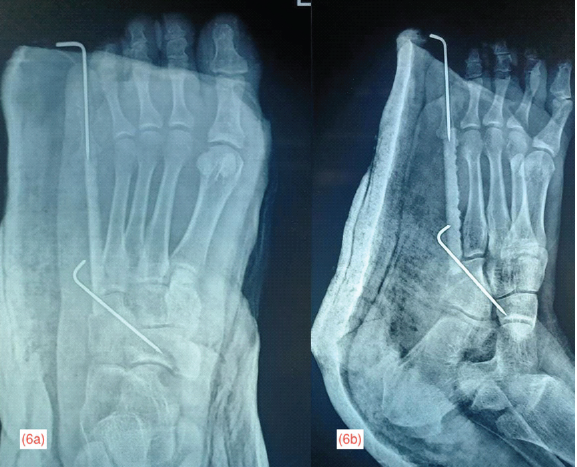

A central trough was created in the base of proximal phalanx of 5th toe and a similar trough was fashioned in the lateral aspect of the cuboid. The graft was wedged into the proximal and distal troughs created and stabilized using K-wires and further protected with below-knee cast. Fig. 6

Figure 6: Immediate post-operative radiograph of left foot in anteroposterior (a) and oblique (b) projection showing the autogenous fibula strut graft secured to the cuboid proximally and to the proximal phalanx of the 5th toe distally using K-wire

shows the immediate post-operative radiograph of the foot protected with below knee cast. Fig. 7 shows the radiograph of the graft donor site in anteroposterior and lateral projection.